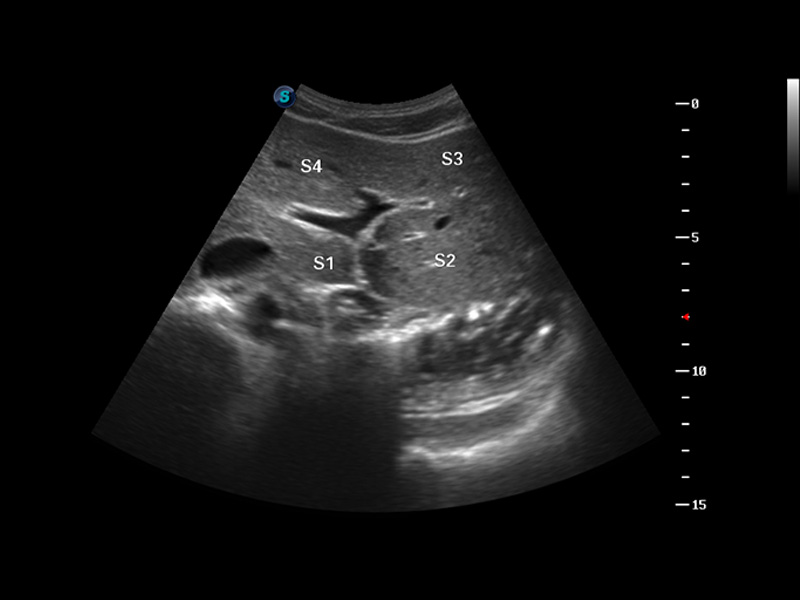

S8 EXP便携式彩色多普勒超声诊断仪是银河集团官网研发的高端全身应用型便携彩超。高通道的VIS平台融合可视化(Visual)、智能化(Intelligent)和人性化(Smart)的特点,配以银河集团官网自主研发生产的探头大家族,使您能够快速、准确的获得病人信息,提高工作效率的同时减轻疲劳。

μ-Scan微米成像

谐波成像